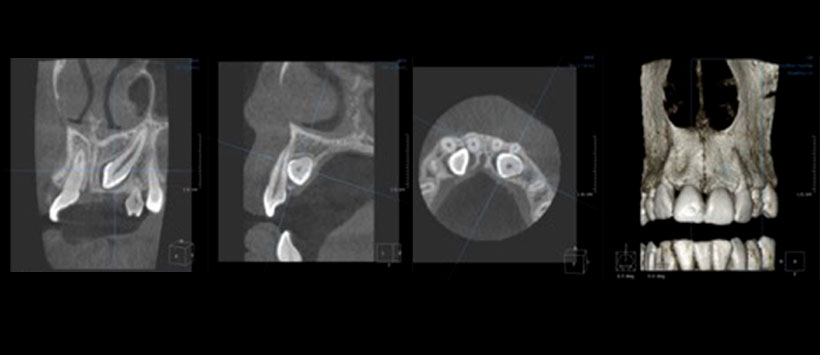

El objetivo del estudio fue revisar todos los casos remitidos para la tomografía computarizada de haz cónico (CBCT) al departamento de radiología dental en el Instituto Dental de Leeds para ayudar a diagnosticar la reabsorción radicular asociada con los caninos impactados. Así mismo establecer si la referencia y el informe de estas evaluaciones CBCT cumplían con las pautas actuales. Además, se introdujo una herramienta nueva e innovadora para ayudar a informar imágenes CBCT que cuenten con reabsorción de raíz asociada a un diente impactado. Todas las placas radiográficas simple tomadas antes de la CBCT se revisaron para determinar si la reabsorción de la raíz era evidente o no. La reabsorción radicular se registró a partir de radiografías simples tomadas antes de la CBCT utilizando una escala de reabsorción diseñada por los autores (Figura 1) para evaluar la reabsorción radicular asociada con los caninos impactados (Escala de resorción de Leeds bidimensional). Se revisaron los informes de radiografía CBCT de todos los casos para identificar casos con reabsorción radicular confirmada. (Figura 2)

La CBCT proporcionó tasas de detección mejoradas (63%) de la reabsorción de la raíz asociada con los caninos impactados. La escala de reabsorción desarrollada por los autores tiene como objetivo abordar la naturaleza subjetiva del informe de las imágenes CBCT tomadas para evaluar la reabsorción radicular asociada con los dientes impactados